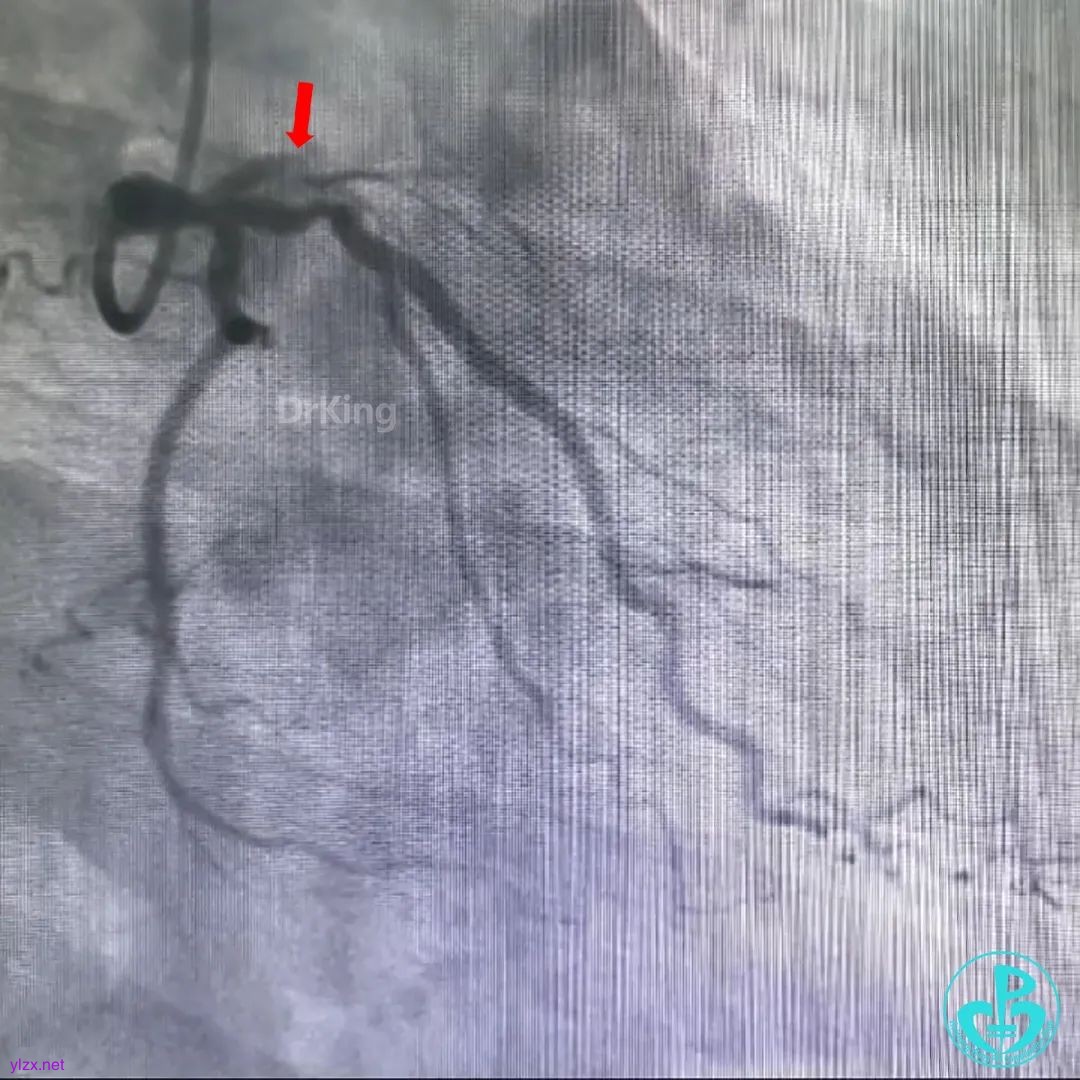

冠脉造影

前降支闭塞,闭塞段大量血栓。